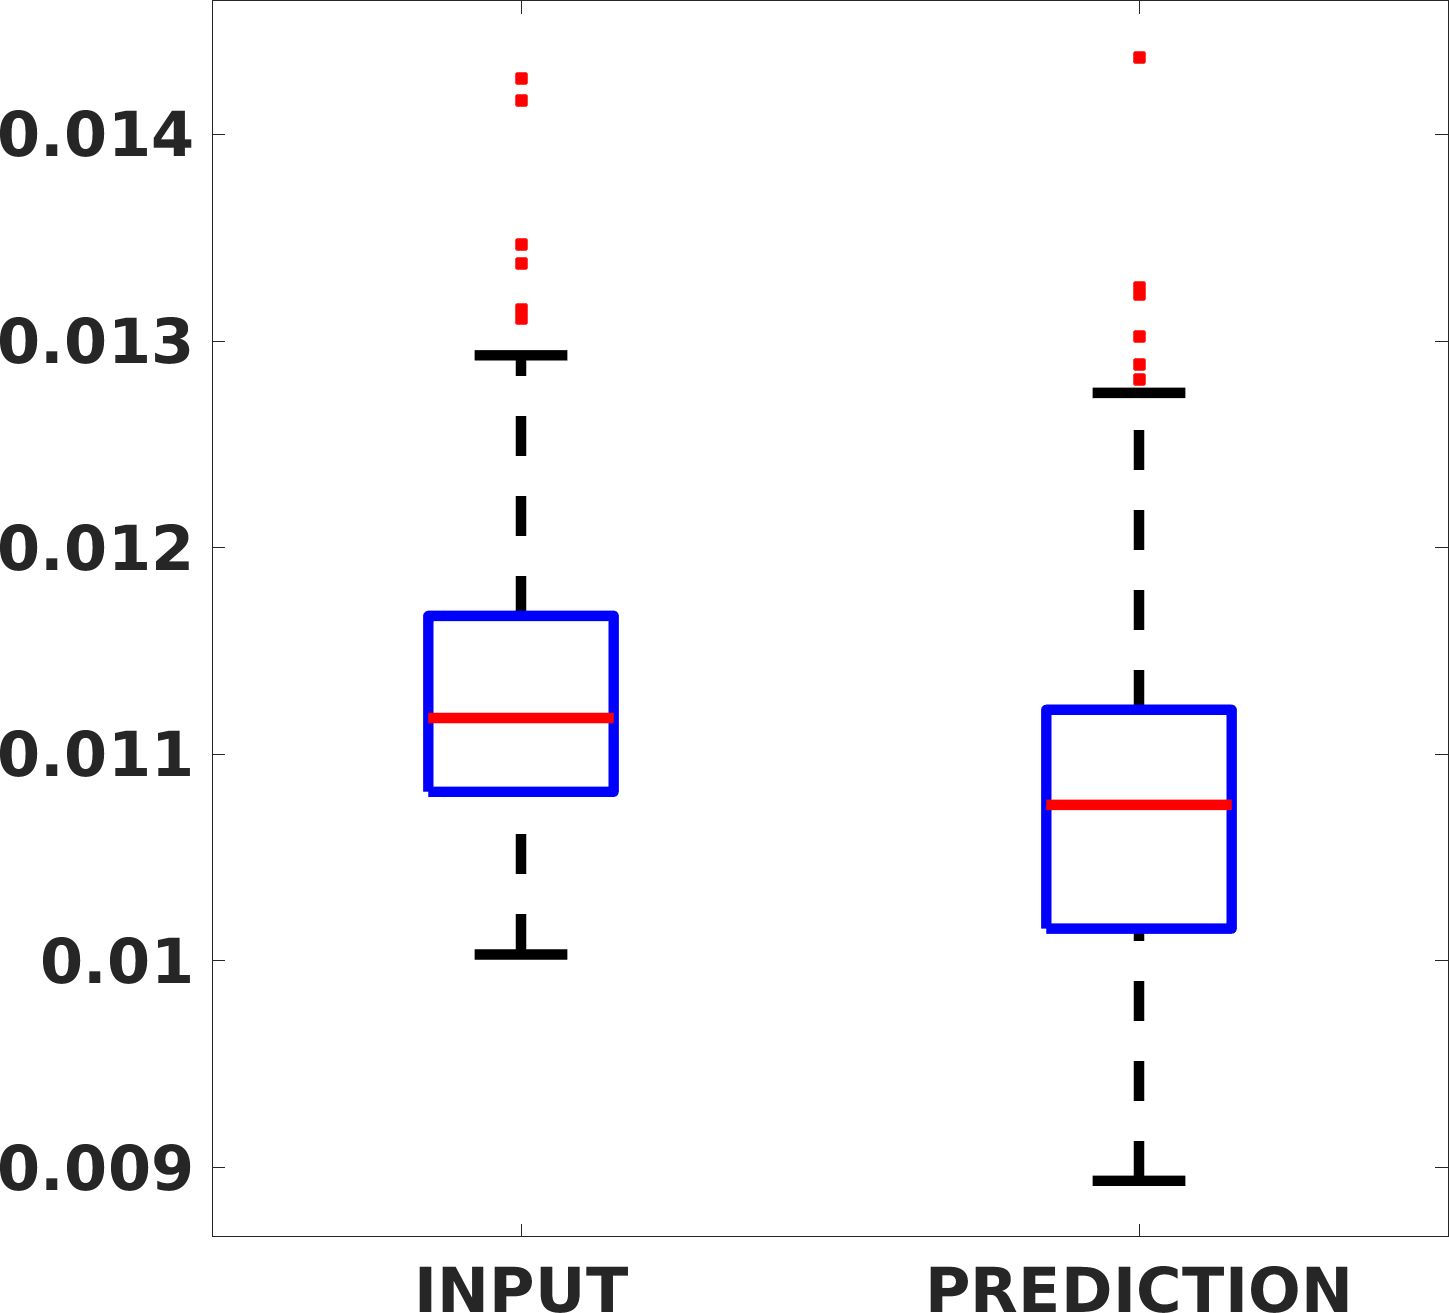

Fig. 7(a-b-c, left) shows the box plot of the statistics of the PSNR on three different anatomical districts, comparing the target images with the prediction and the cubic convolution, respectively. The metrics are computed on a data set of 200 images of the same district and with the same up-sampling factor. We report that the PSNR median value improves of on obstetric 2X raw images, on cardiac 2X raw images, and on abdominal raw 4X images.

Fig. 7(a-b-c, right) shows the histogram of the absolute value of the error with respect to the target image, of the prediction and Cubic convolution results, respectively. The histograms show the number of pixels where the prediction error is lower than 5 (i.e., the first bin of the histogram), which means very similar to the target when visually analysing the images. From the Cubic convolution to the predicted images, this value increases of on obstetric 4X raw images, on cardiac 4X raw images, and on abdominal 4X raw images.

Fig. 8 shows the box plot of the SSIM (a-b-c, left) and MAE (a-b-c, right) quantitative metrics, as performed for PSNR metric. Also, these metrics show that our method improves the results of Cubic convolution both in terms of average value and variability. For example, the SSIM median value improves of on obstetric 4X images and the MAE median value improves of on cardiac 2X images.